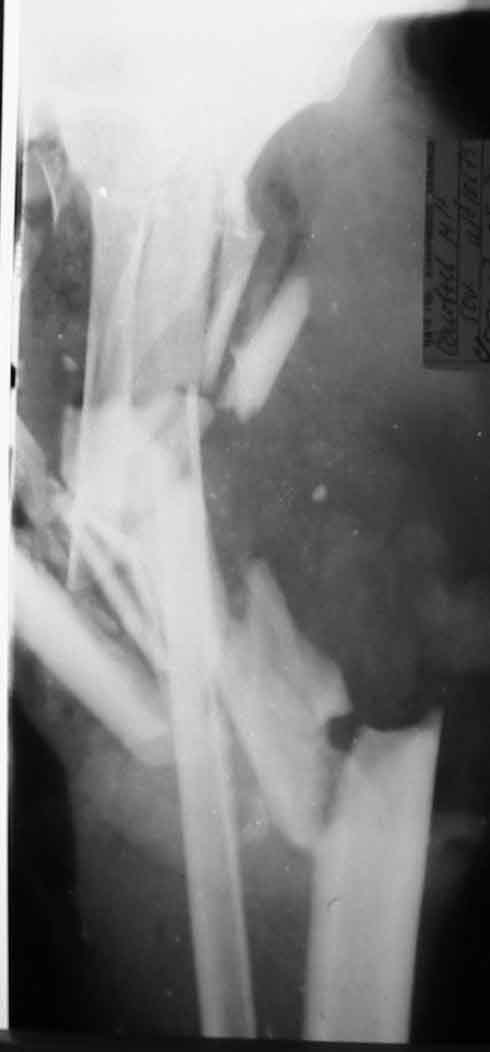

Больной С., 50 лет, строитель, поступил в 64 ГКБ 17.05.02., доставлен СП.Травма за 1 час до поступления на работе на ноги пострадавшего наехал трактор. При поступлении больного тяжелое, сознание спутаное, больной возбужден, не критичен. Кровотечения нет. Кожные покровы бледные. Пульсация на периферических артериях слабо определяется. АД 80/60 мм рт ст. Справа закрытый перелом большельшеберцовой без смещения.На Р-граммах левой голени многооскольчавый перелом костей с/3 в/3 голени (см 1)). Другие сегменты не пострадали.ДЗ. Открытый Многооскольчатый раздробленный перелом костей левой голени. Разможжениемягких тканей левой голени. Закрытый перелом с/3 большеберцовой кости правой голени со смещением. Вывих головки малоберцовой кости. Травматический шок 2-3 ст. Минуя приемное отделение больной поднят в экстренную операционную. После выведения больного из шока выполнена ПХО, и учитывая разможжение мягких тканей левой голени и многооскольчатый характер перелома - ампутация левой голени на границе в/3, экзартикуляция м/берцовой. Решено было максимально сохранить длину конечности. Ранане ушивалась, наложены провизорные швы (см 2, 3).На правую голень фиксирована разрезной гипсовой повязкой.Производились перевязки Н2 О2 , повязки с левомеколем, по мере спадения отека дозировано подтягивались провизорные швы. По состоянию на 24.05.02 Состояние больного удовлетворительное, субфибрильная лихорадка.Местно: в рану выстоят опил б/берцовой кости, кожный лоскут "болеет", некроз мышц иподкожной клетчатки в наружном углу раны (см 4).Вопросы:-Оправдана ли сберегательная тактика при поступлении?-В последующем имеет ли смысл постараться сберечь максимально возможную длинусегмента? -Если да то как заместить дефект тканей?-Если нет то какой вид ампутации выбрать и на каком уровне?Глеб КоробушкинАспирант Кафедры травматологии и ортопедии РГМУ, Москва

27.05.02. Выполнена Некректомия, вторичная хирургическая обработка раны

культи в/3 левой голени.

В условиях гнойной операционной произведена проводниковая анестезия бедренного, седалищного нервов Sol. Lidocaini 1%-50,0. Сняты провизорные

швы. При ревизии раны выявлено рана по передне-нижней поверхности культи левой голени, в рану выстоит опил большеберцовой кости, рана 17х7 см

веретенообразной формы. В наружном углу раны имеется краевой некроз остатков камбаловидной мышцы, краевой некроз кожного лоскута. Рана промыта перекисью водорода, водным раствором хлоргекседина, задний лоскут частично отделен от

места его прилежания, иссечены некротизированные мышечные ткани в пределах здоровых. Рана обработана ультразвуком, промыта водным хлоргекседином. Края раны ушиты, в середине раны наложены провизорные швы. Повязка с левомеколем.